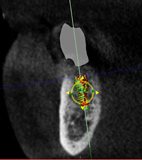

(12.) Postoperative CBCT image of actual implant placement at site No. 21.

Figure 12

(13.) Postoperative CBCT image of actual implant placement at site No. 19.

Figure 13

A healthy 60-year-old female presented for an emergency evaluation because she was experiencing pain associated with tooth No. 20. It was mobile, malposed, and given a diagnosis of irreversible pulpitis. In addition, teeth Nos. 19 and 21 had been missing for more than 5 years. After the evaluation, a discussion revealed that the patient desired implant reconstruction of the lower left quadrant. During this initial visit, a CBCT scan was obtained, and the virtual restoration-driven implant planning was completed, confirming that extraction of tooth No. 20 with robot-assisted immediate implant placement at the sites of teeth Nos. 19 and 21 was a viable option (Figure 9 through Figure 13). Splint placement, CBCT capture of the fiducial array, calibration, and landmark confirmation were completed as described in the first case report. Following the administration of intravenous sedation and local anesthesia, tooth No. 20 was atraumatically extracted. Flap access was obtained from the site of tooth No. 18 to the site of tooth No. 22, and robot-assisted surgical implant placement was completed at the sites of teeth Nos. 19 and 21. Intraoperatively, guide pins were placed to evaluate the position of the proposed osteotomies, and it was determined that both implants should be tilted buccally by 0.4 mm. The necessary changes were made in the software application, and the new implant placement plan was immediately ready for robotic implementation. The implants were robotically delivered to their planned positions at the sites of teeth Nos. 19 and 21 and torqued to initial stability at 50 Ncm and 45 Ncm, respectively (Figure 14 and Figure 15). Healing abutments were placed, and the tissue was closed primarily. In this case, robotic assistance facilitated the performance of surgery on the same day that the patient initially presented and permitted intraoperative modifications to be made.